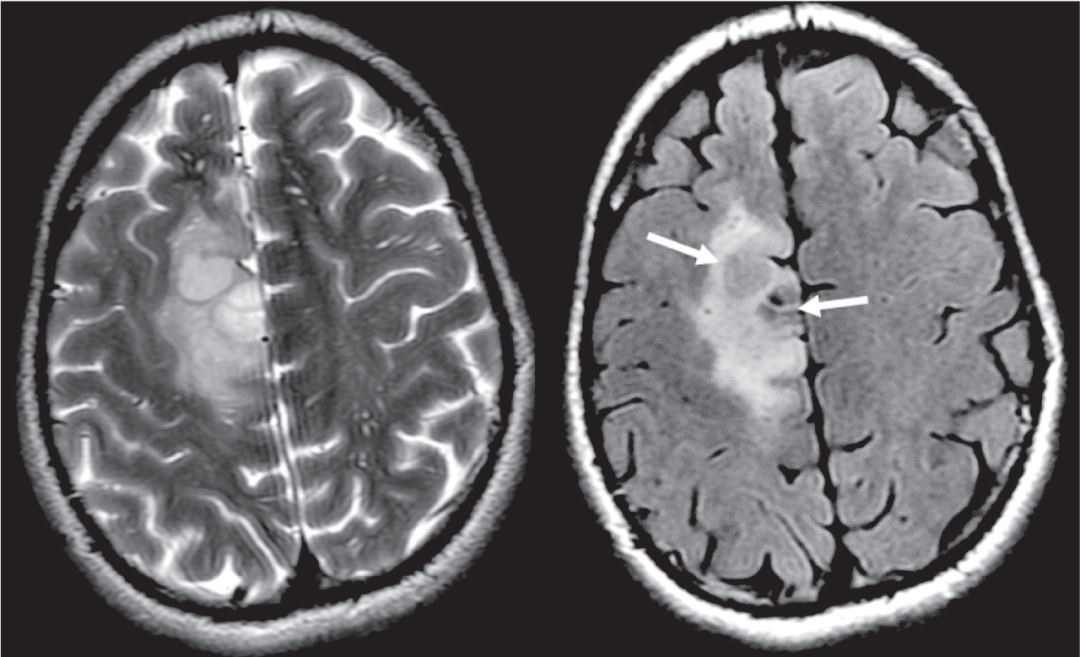

回过头看本病例,肿瘤在 T2WI 呈主体均质高信号,FLAIR 主体呈低信号,周围环形高信号;术后病理为星形细胞瘤 IDH 突变型。

2 例星形细胞瘤 IDH 突变型,均表现为 T2-FLAIR 错配,注意 FLAIR 低信号可以是均匀或不均匀